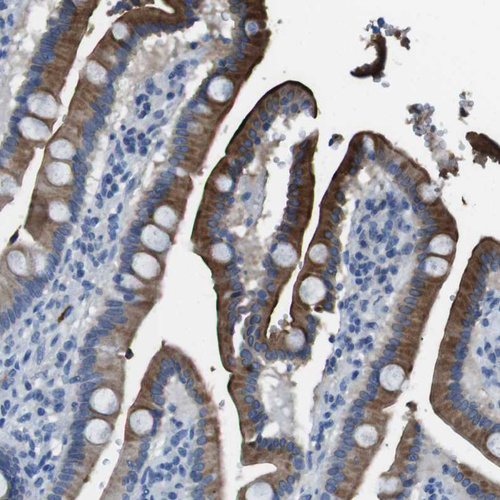

Immunohistochemical staining of human duodenum shows moderate membranous positivity in glandular cells.